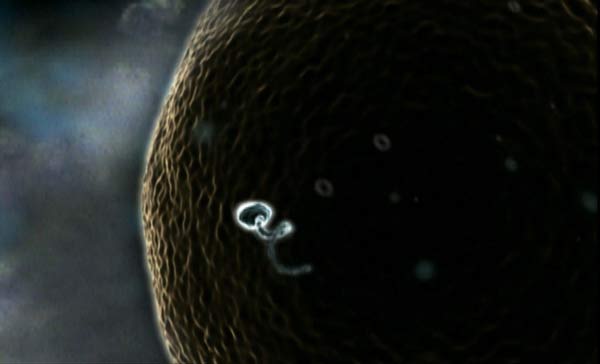

Primeras semanas. Aún no han aparecido los primeros rasgos humanos y, por su fisonomía, podría tratarse de cualquier mamífero.

Primeras semanas. Aún no han aparecido los primeros rasgos humanos y, por su fisonomía, podría tratarse de cualquier mamífero.